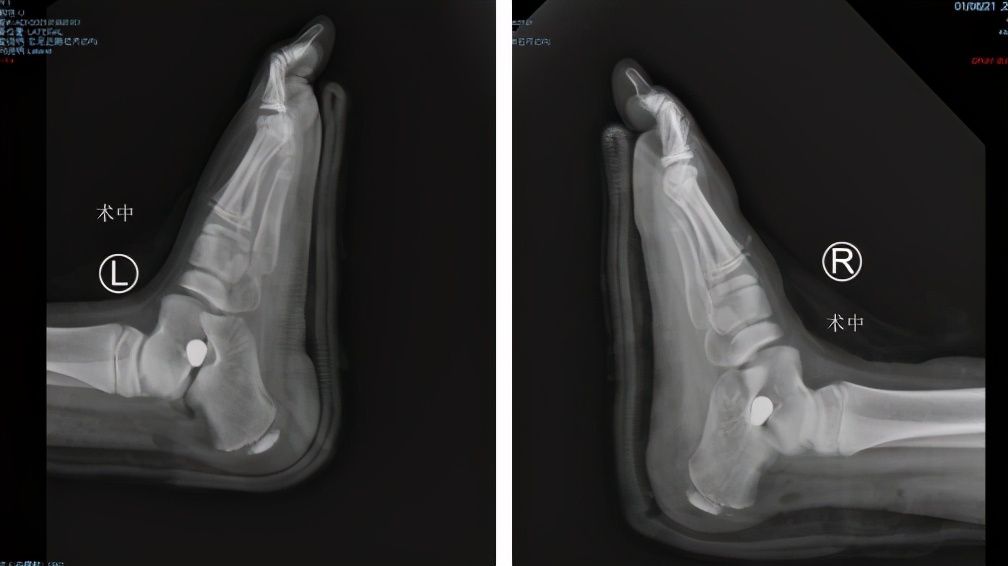

第二天,曹广超主任王岩岩手术团队为小患者进行了双侧距下关节固定+跟腱松解术。该手术创伤小,只在跟腱表面取3个0.5cm小切口;另取外踝前下方1cm切口,放置制动器以稳定距下关节,术中即刻拍片显示足弓明显改善,扁平足畸形得到了完全纠正,并且足背较小切口,不会遗留大的瘢痕,不影响美观。手术很成功,家长很满意。